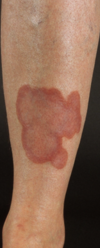

En 45-årig mand med type 1 diabetes henvender sig til sin praktiserende læge med et blåviolet område på forsiden af ve. underben. Han bemærkede det for adskillige måneder siden og det har stort set ikke ændret sig siden.

Hvad er den sandsynlige diagnose ?

- a. Kavernøst angiom

- b. Forandringer sekundært til osteomyelitis med fistel fra tibia til huden

- c. Kroniske vaskulitis forandringer

- d. Necrobiosis lipoidica

- e. Hæmophili

d. Necrobiosis lipoidica

En 45-årig mand med type 1 diabetes henvender sig til sin praktiserende læge med et blåviolet område på forsiden af ve. underben. Han bemærkede det for adskillige måneder siden og det har stort set ikke ændret sig siden. Hvad er den sandsynlige diagnose?

a. Kavernøst angiom

b. Forandringer sekundært til osteomyelitis med fistel fra tibia til huden

c. Kroniske vaskulitis forandringer

d. Necrobiosis lipoidica

e. Hæmophili

d. Necrobiosis lipoidica